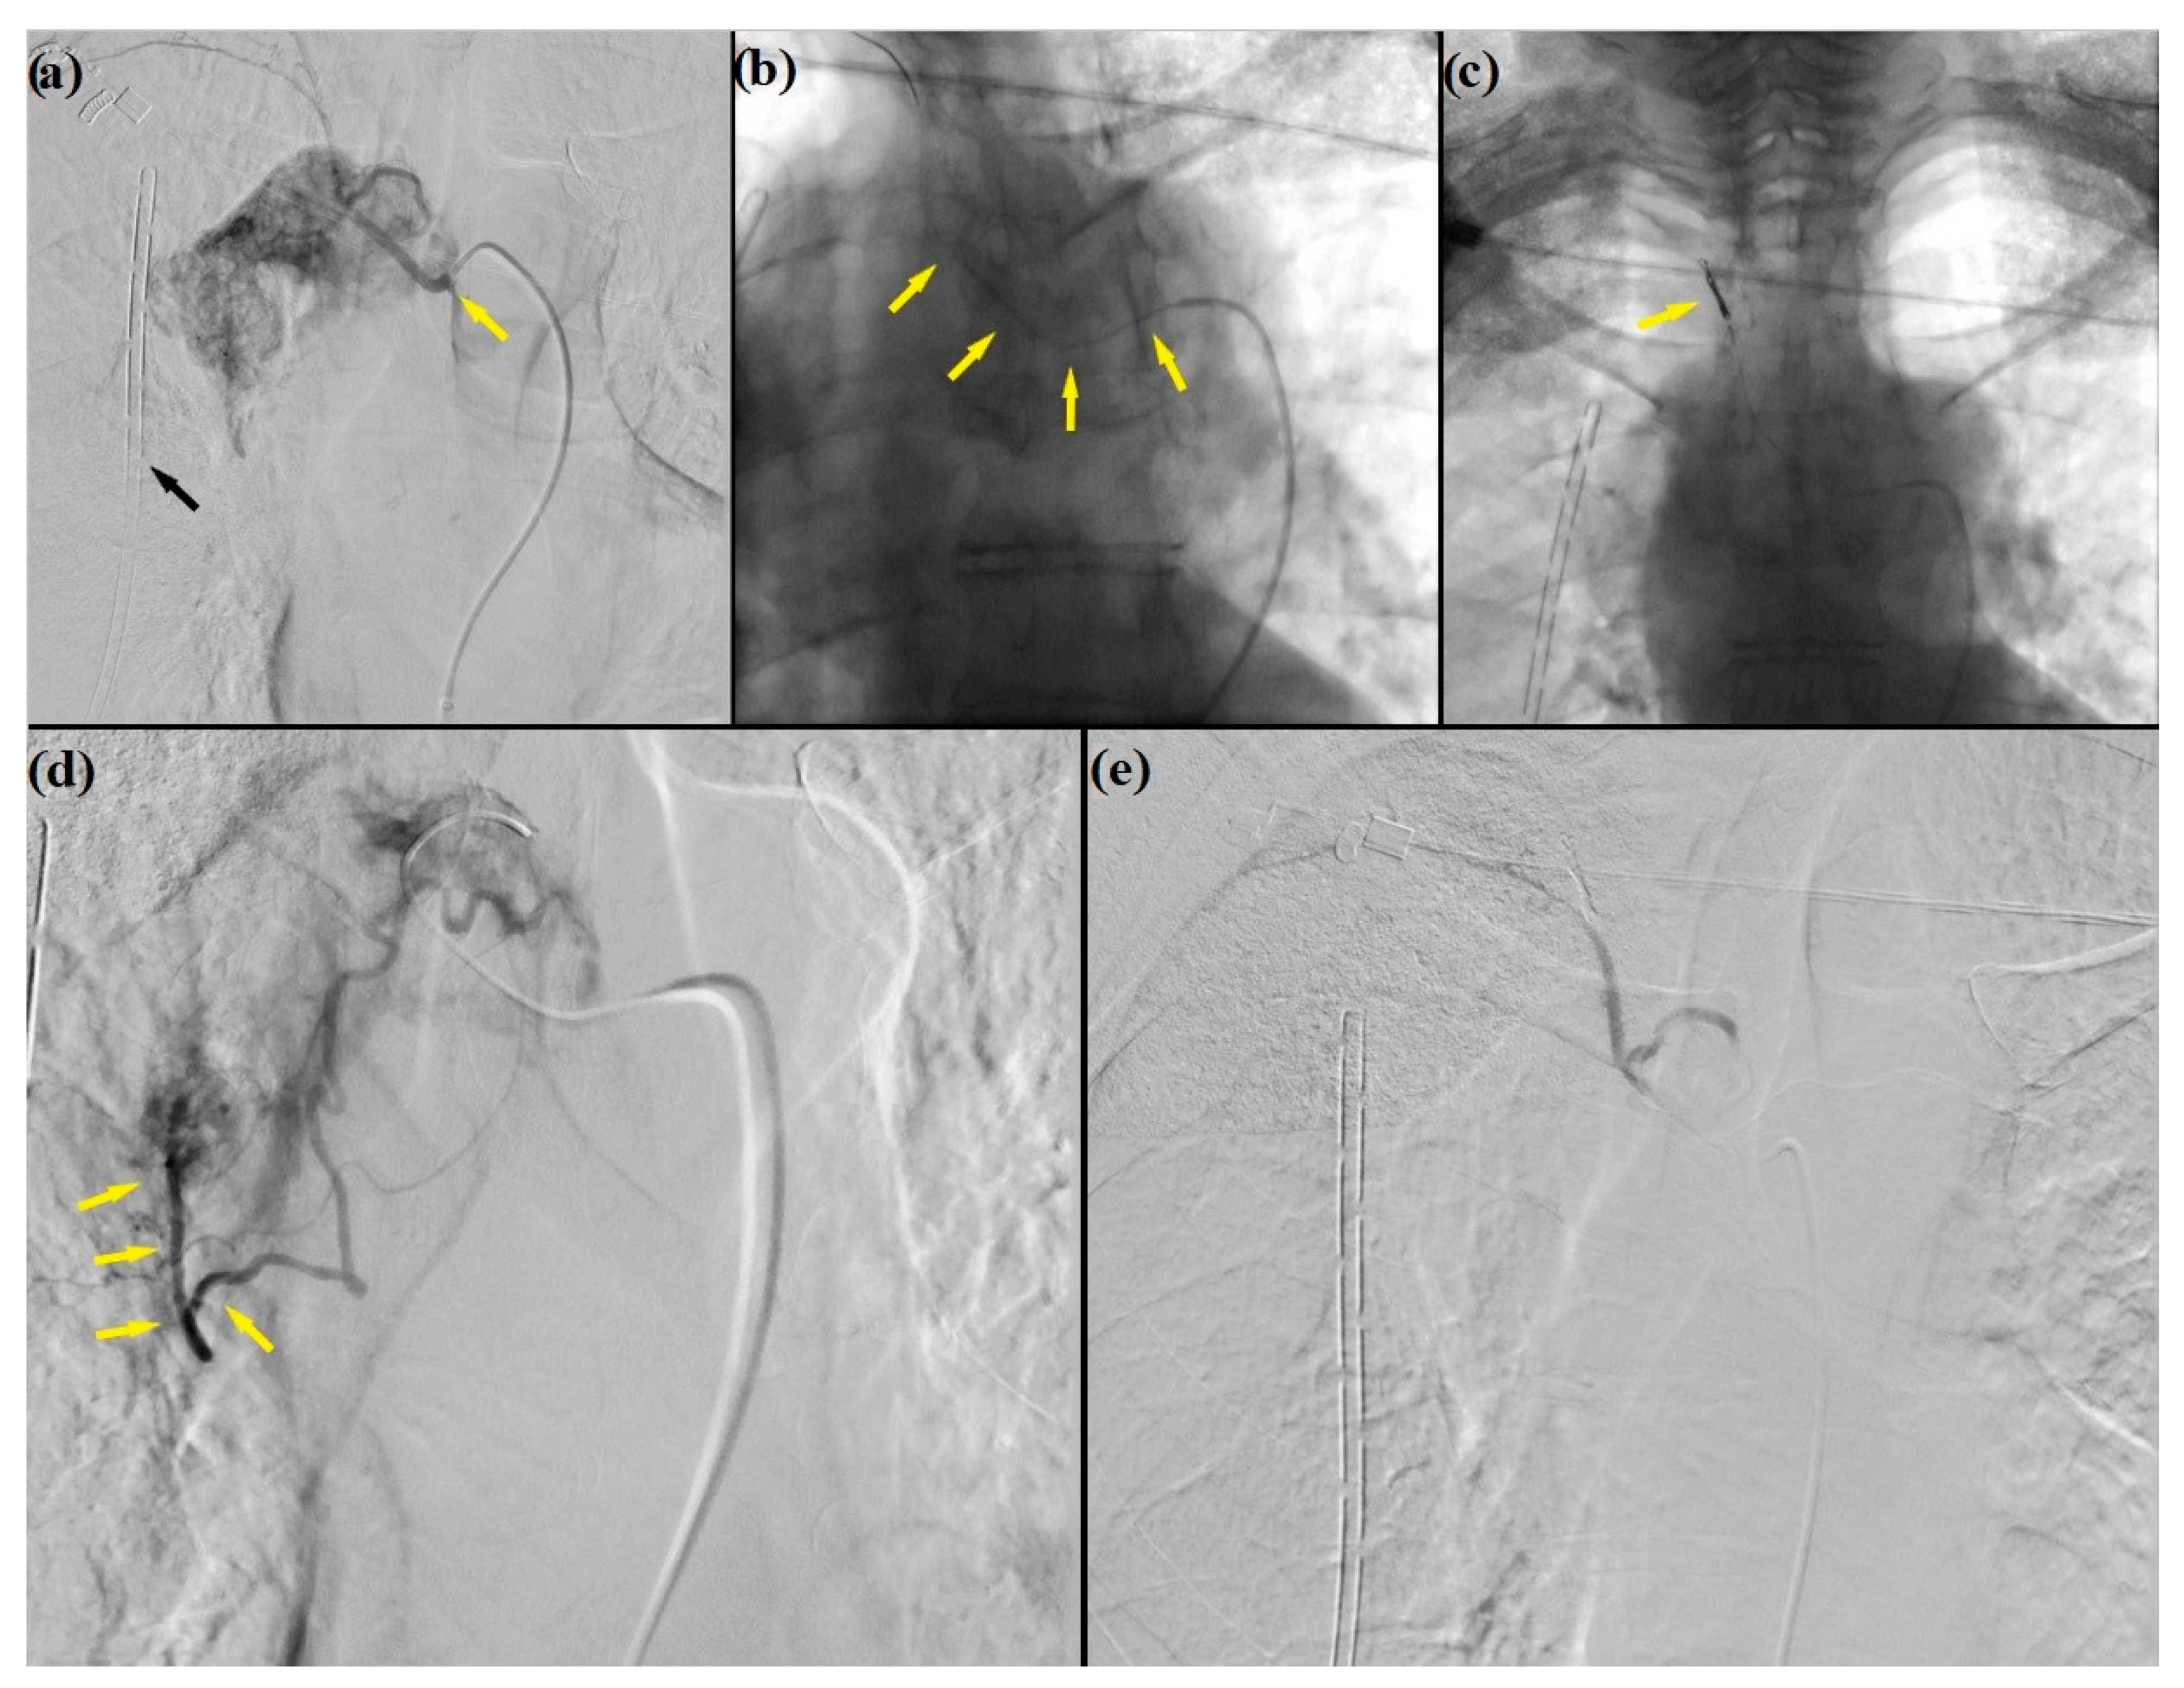

2. Case Presentation